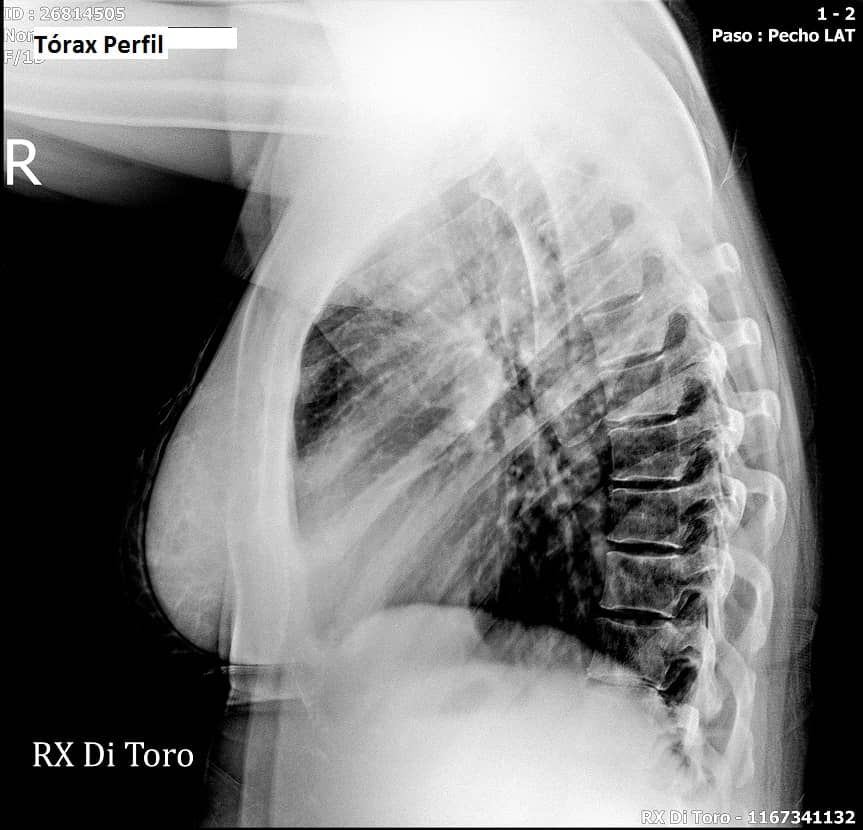

Utilizamos sensores Flat Panel, que nos permiten acortar al Máximo el tiempo de exposición (Dosis de Radiación) y obtener la adquisición inmediata de las imágenes.